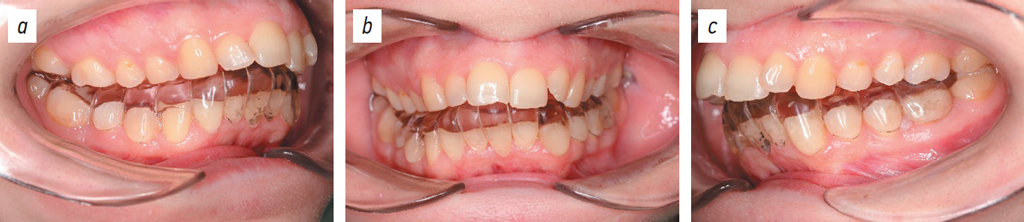

Fig. 2. Dental arches: lateral right projection (a), posteroanterior projection (b), lateral left projection (c).

Рис. 2. Зубные ряды: боковая правая проекция (a), передняя проекция (b), боковая левая проекция (c).

On examination: attrition of upper and lower incisal edges, cusps of canine teeth, and occlusal surfaces of molars. V-shaped constriction of the maxillary arch. Crowding of the upper and lower incisors. The maxillary and mandibular labial frenula and the buccal frenula are attached at the center of the alveolar part. Overeruption of tooth 14 (ISO 21). Occlusal plane deformation. The overjet measures 11.6 mm. The maxillary midline is displaced 3.5 mm to the left relative to the facial midline. Angle Class II molar relationships. TMJ clicking on the left when opening the mouth. TMJ clicking and popping on the left on palpation via the external auditory meatus. The medial pterygoid muscle on the right is mildly tender on palpation. The lateral pterygoid muscle on the right and left is tender on palpation. The posterior discotemporal ligament on the left is tender on palpation. When swallowing saliva, the tongue is positioned between the upper and lower teeth (Figs. 1–3).